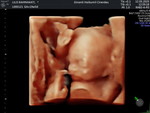

Hamil 39 week keluar flek darah,langsung periksa ke dokter atau nunggu kontraksi intens dulu ya bun?

sedang mengandung